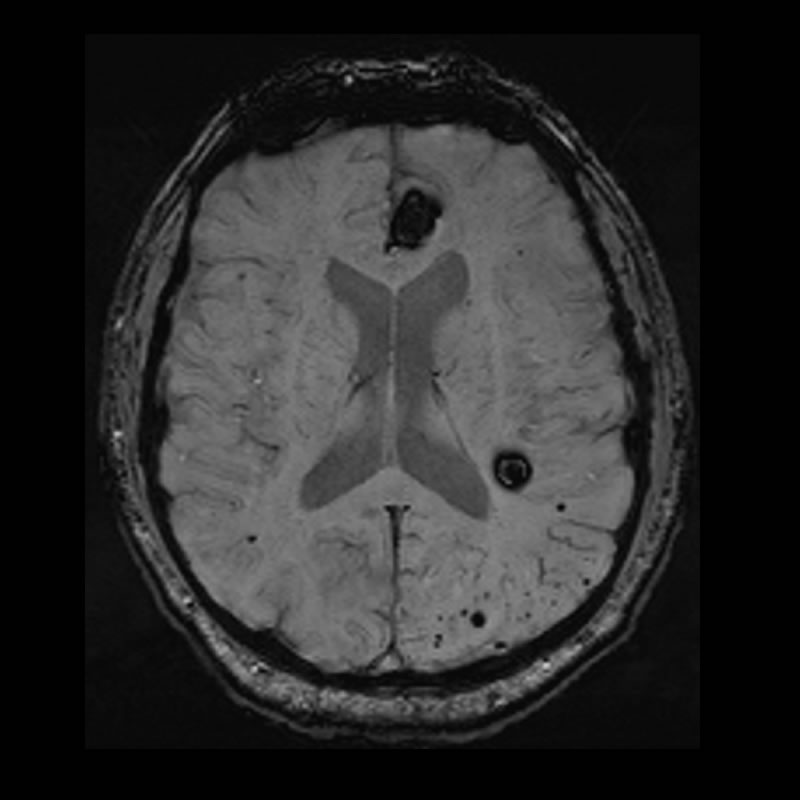

Junio 2021. Instituto Oulton Hombre de 55 años, con antecedentes de cardiopatía y FA, consulta por sindrome convulsivo.